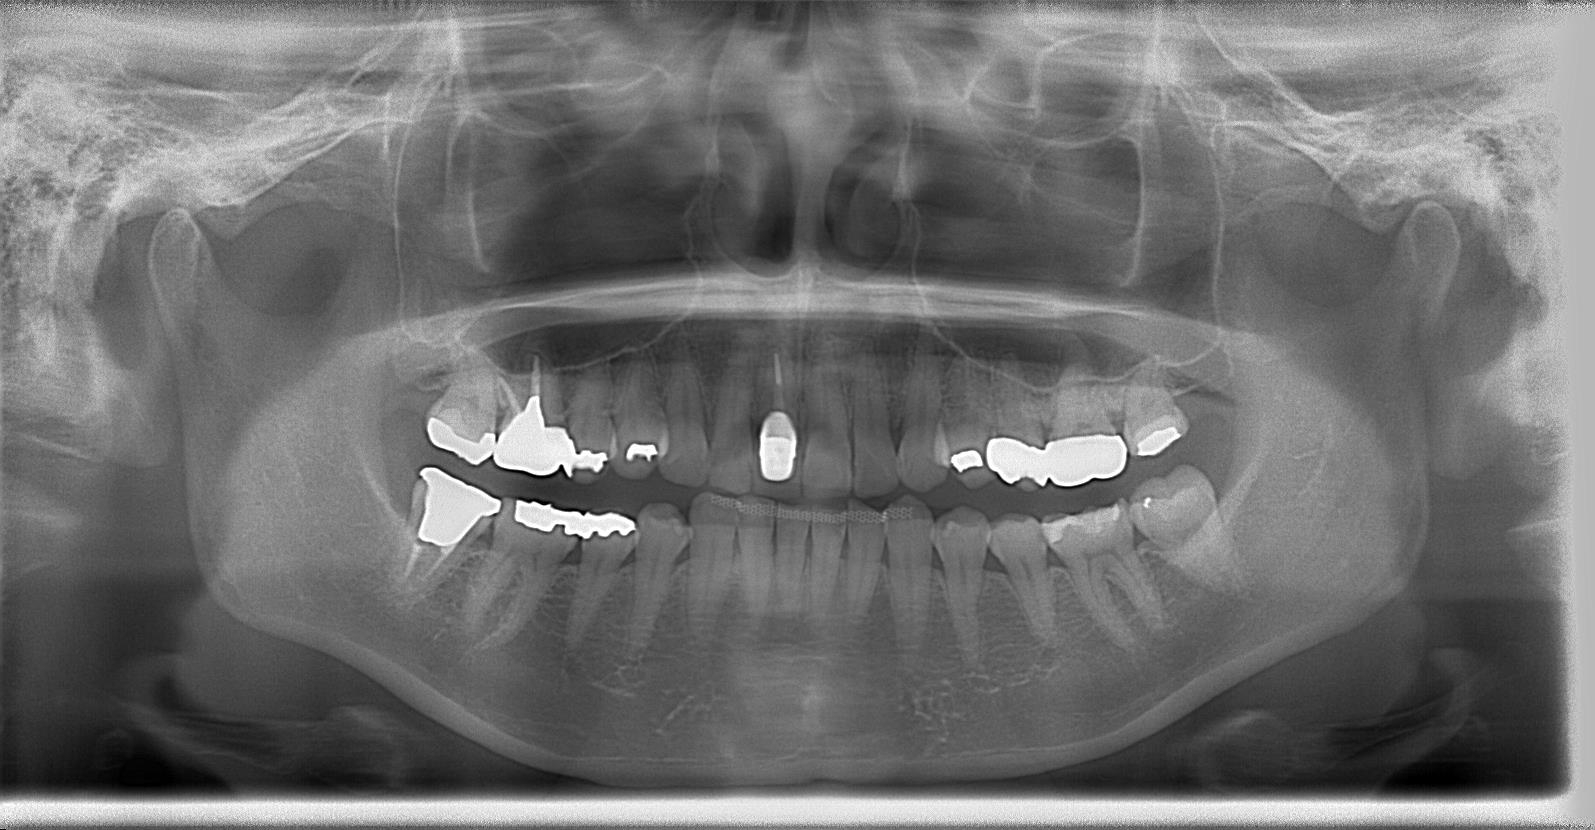

術前のパノラマレントゲン写真